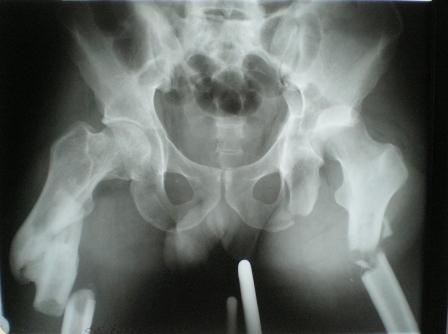

Уважаемые коллеги! Помогите пожалуйста в лечении сложного клинического случая Пациент 33 лет поступил 1.02.08 с диагнозом: Множественная травма. Т-образный перелом свода, перелом заднего края правой вертлужной впадины. Поперечный подвертельный перелом диафиза, подвздошный вывих правого бедра. Поперечный подвертельный перелом диафиза на фоне консолидированного косого перелома в\3 левого бедра в порочном положении. Открытый краевой перелом надколенника правого коленного сустава. Открытый оскольчатый перелом н\челюсти. Закрытый неосложненный перелом V ребра справа. В настоящее время больной компенсирован. Планируем: в положении больного на спине выполнить БИОС левого бедра ретроградно. После повернуть на левый бок и выполнить БИОС правого бедра антеградно одновременно с Y-образным доступом к вертлужной впадине. После - остеосинтез вертлужной впадины реконструктивными пластинами. Посоветуйте пожалуйста: 1. возможно ли выполнить все 3 операции одномоментно? 2. если возможно, то м\б начать операцию на стороне более тяжелого повреждения? Как при этом укладывать, и каким способом оперировать? 3. стоит ли выполнять БИОС левого бедра при условии, что если выбрать штифт длинной до б\вертела, то при введении проксимальный конец пройдет мимо б\вертела по задней поверхности?Заранее благодарен. Гринь Алексей.

Глубокоуважаемые коллеги! Благодарю за полезные советы, которые нам очень помогли в выборе оперативной тактики пациента. 13.02.08 мы выполнили первый этап оперативного лечения этого больного. Вначале зафиксировали левое бедро АВФ Гофмана

(главный травматолог области достал из каких-то «анналов», первый раз в жизни увидел этот аппарат в живую). После наложения «ДРУ Челнокова» выполнили ЗИО правого бедра реконструктивным штифтом Chm. Далее уложили пациента на левый бок и выполнили остеосинтез вертлужной впадины. Ограничились задне-латеральным доступом без отсечения вертела, чтобы не утяжелять операцию. Результат прилагается.